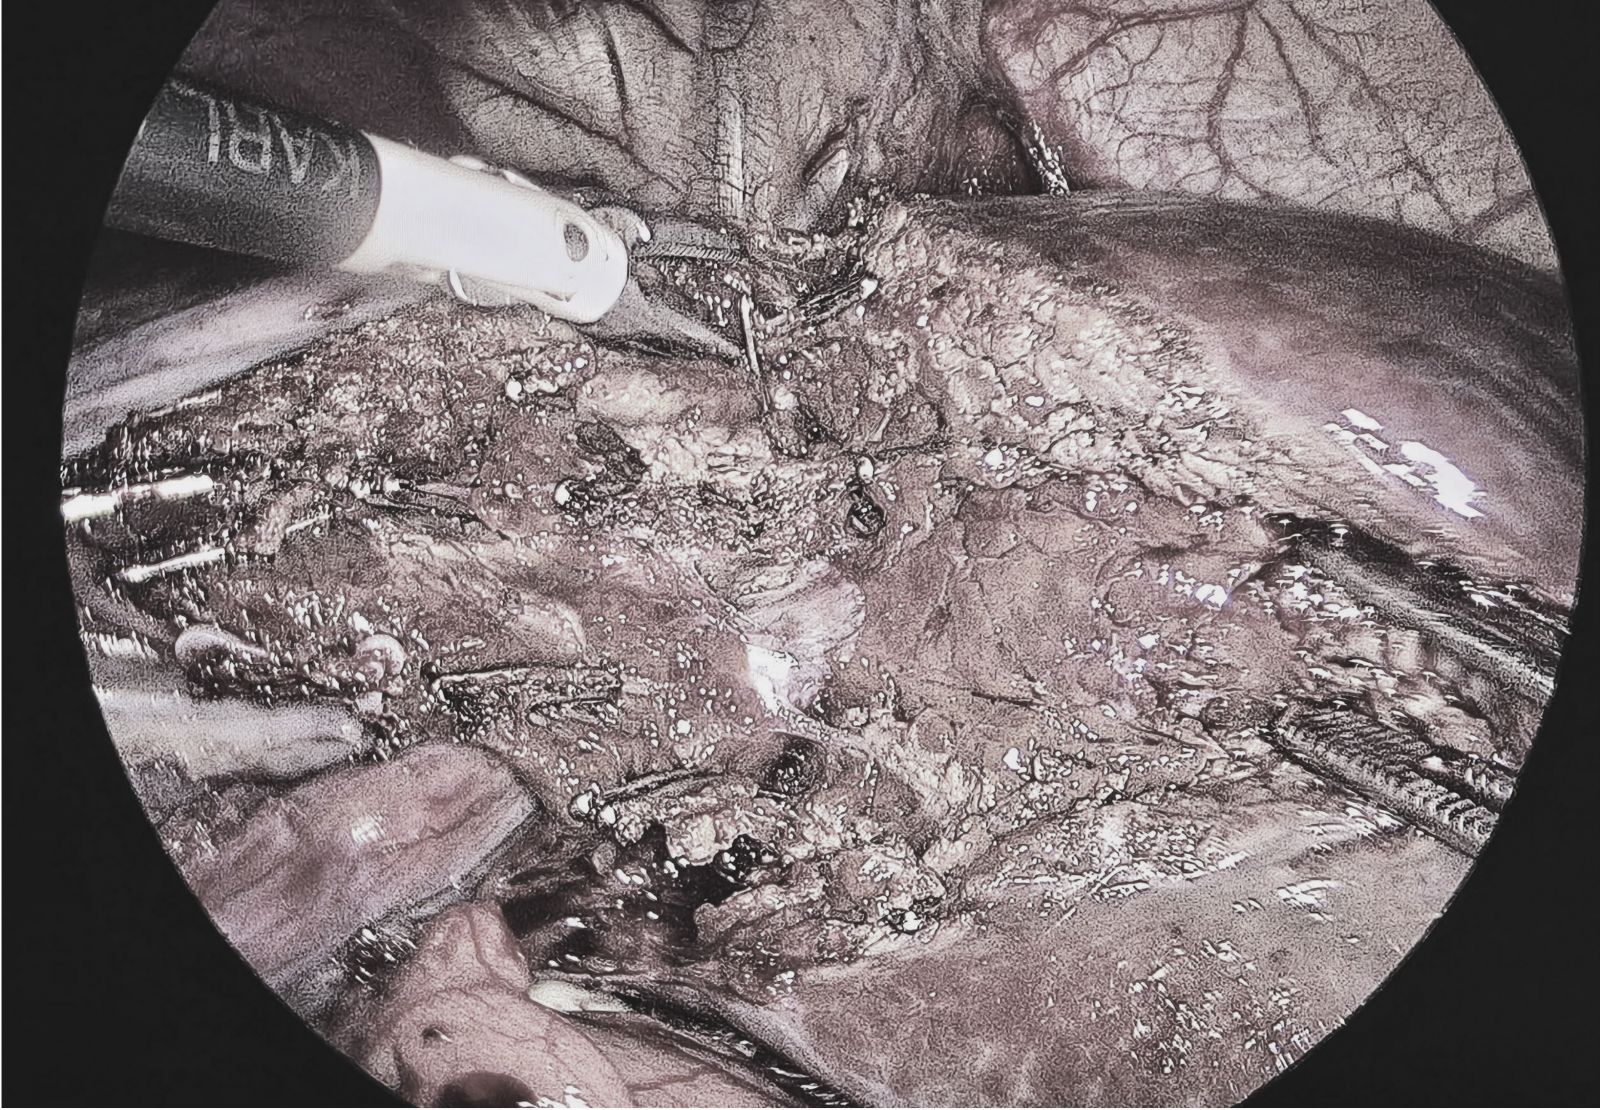

Hình ảnh nội soi cắt gan.

Sau khi thực hiện thêm các xét nghiệm cần thiết và hội chẩn chuyên môn, người bệnh được chỉ định phẫu thuật nội soi cắt phần gan có khối u. Ca mổ do ê-kíp Khoa Ngoại tổng hợp thực hiện, đảm bảo an toàn, hạn chế xâm lấn, giúp người bệnh ít đau và nhanh hồi phục.

BSCKII. Trần Văn Do – Trưởng Khoa Ngoại tổng hợp, Bệnh viện Việt – Hàn Đà Nẵng cho biết: “Phẫu thuật nội soi cắt gan là kỹ thuật phức tạp, đòi hỏi bác sĩ có kinh nghiệm và trang thiết bị hiện đại. Ưu điểm của phương pháp này là vết mổ nhỏ, ít đau, giảm nguy cơ biến chứng và rút ngắn thời gian nằm viện”.